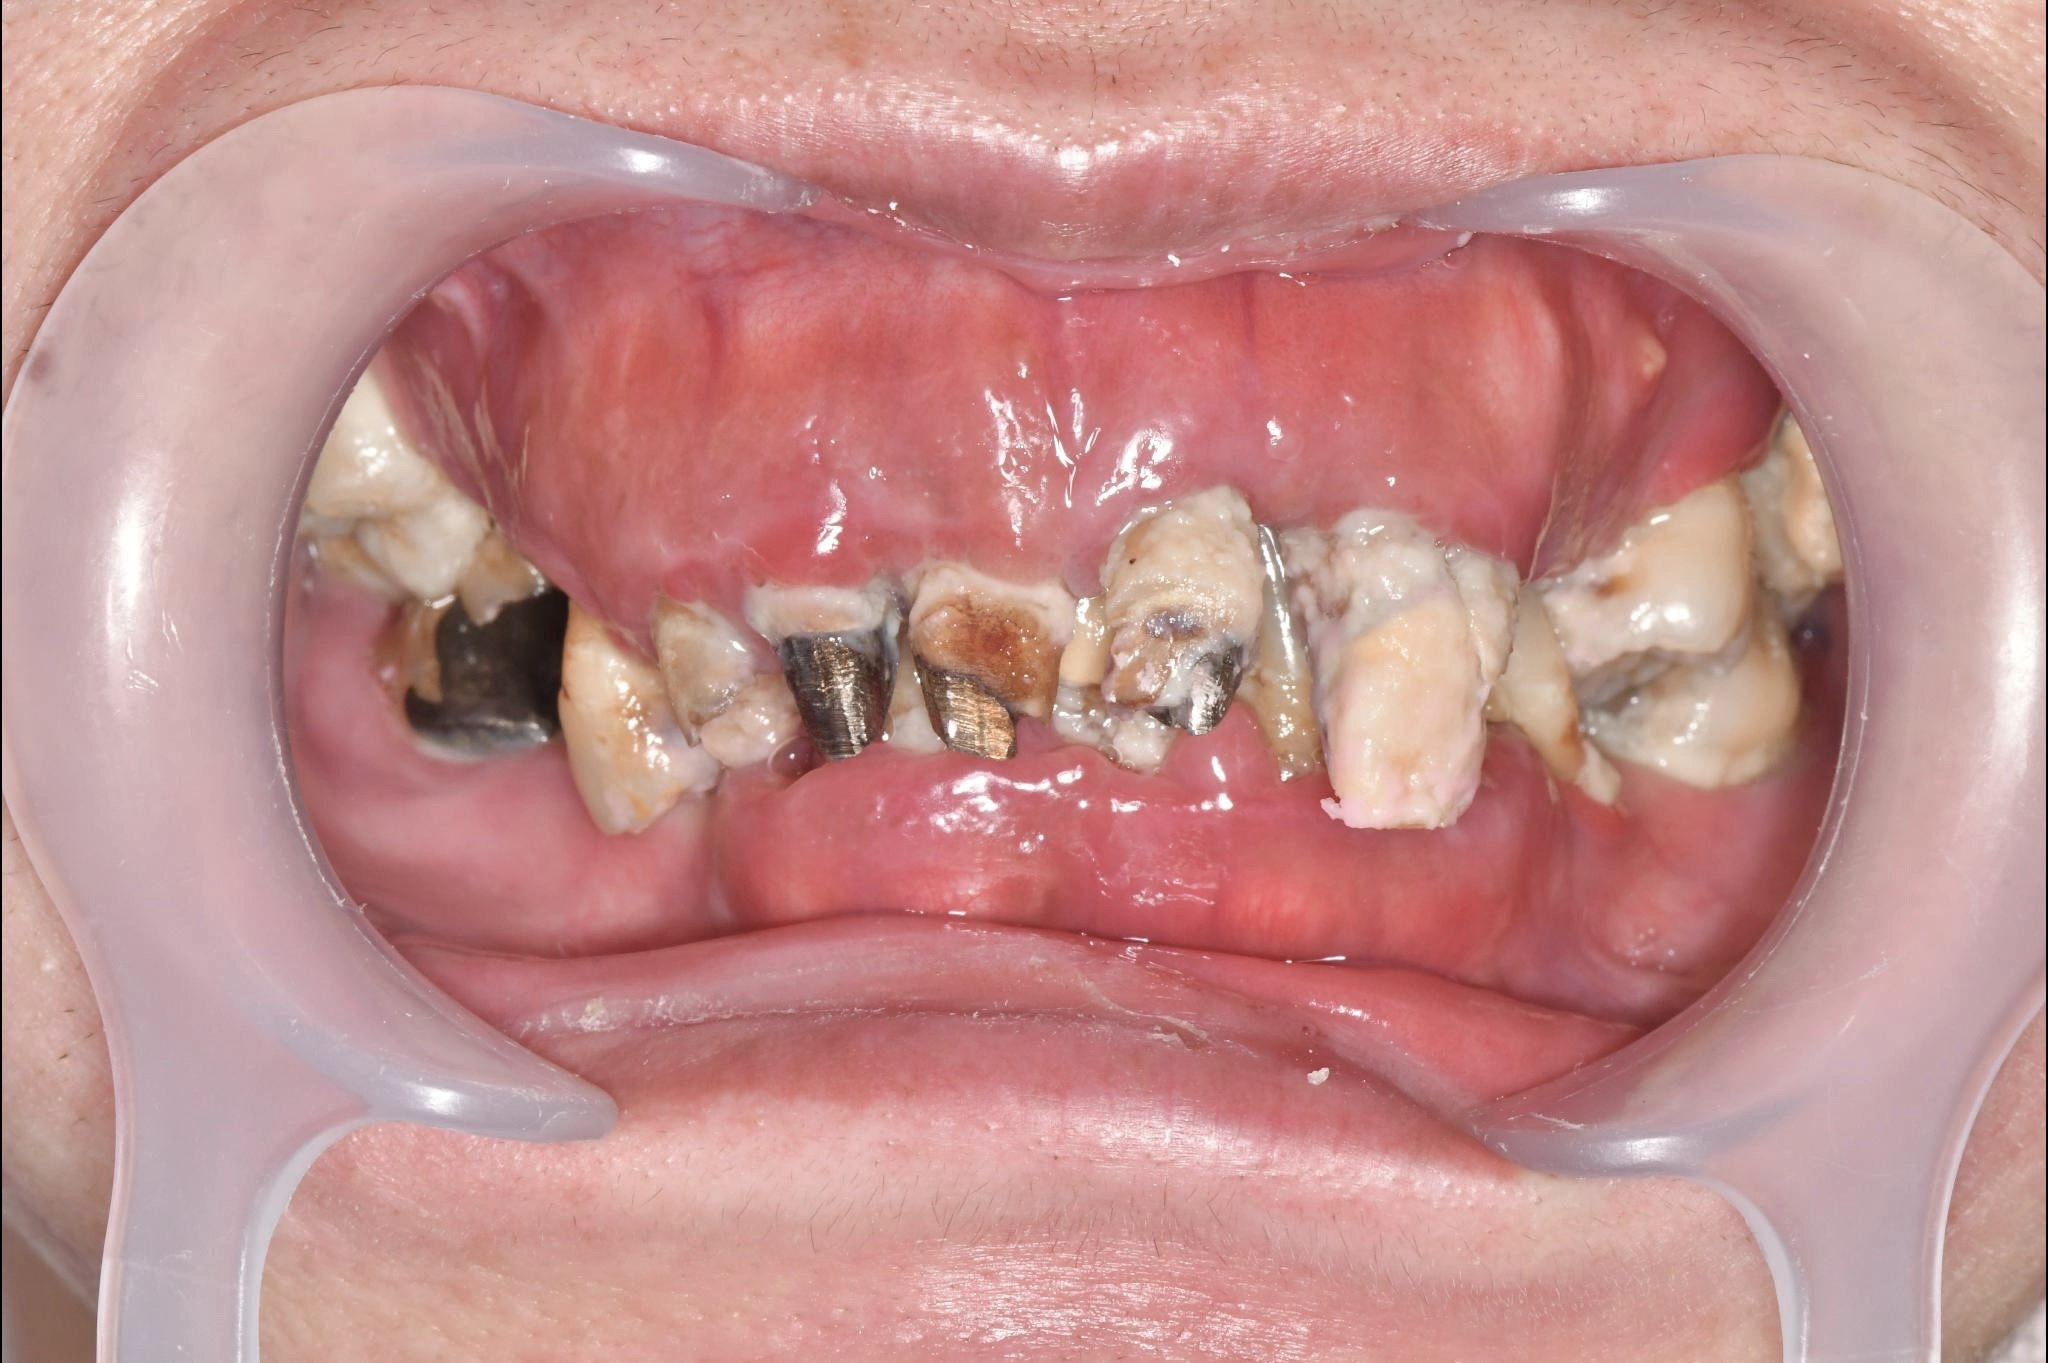

大分県 45歳(女性)

「マスクを外して人付き合いをしたい」

術前

内容 :上下顎オールオン4ザイゴマ0

費用 :4,365,900円

※モニター価格

期間 :半年

リスク:出血・腫れ・痺れ・痛み

「何度も通って恥ずかしい思いを長引かせたくない」という気持ちがありましたので、治療期間が短く、たった1日で固定式の歯が入ることがとても魅力的でした。

手術に対しては強い恐怖心を持っていましたが、実際には術中の記憶はほとんどなく、痛みを感じることもなく無事に終えることができました。

これまでは口元を気にして人との接触を避けていましたが、「笑顔で話したい」という明るい気持ちになれました。